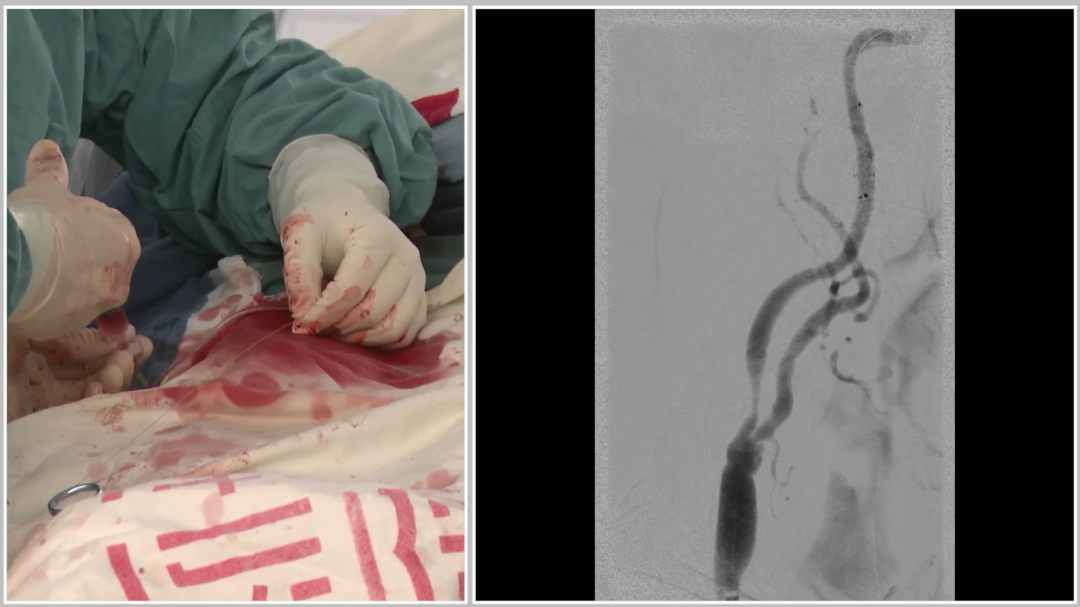

★ 收尾与验证

回收保护伞:检查伞内无明显碎屑,排除栓塞风险;

最终造影:支架血流通畅,颅内血流较术前明显改善(侧位及汤氏位对比显著);

安全撤鞘:导丝保护下撤出长鞘,避免“甩鞭效应”导致栓塞;

穿刺点处理:采用Proglide血管封堵器缝合,手术结束。

术后情况

最终对比患者术后无神经系统并发症(如脑梗、脑出血),无其他不良事件;术后重点监测血压,避免低灌注风险;对比术前术后造影,右侧颈内动脉狭窄显著改善,颅内血供明显提升。